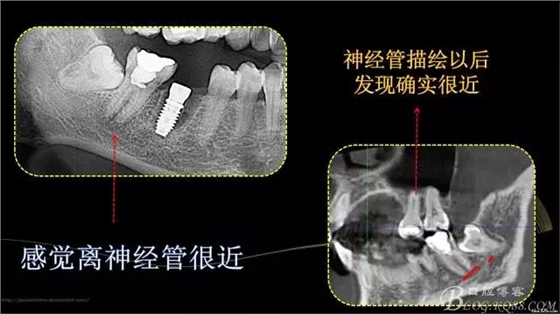

640.webp.jpg

640.webp (1).jpg